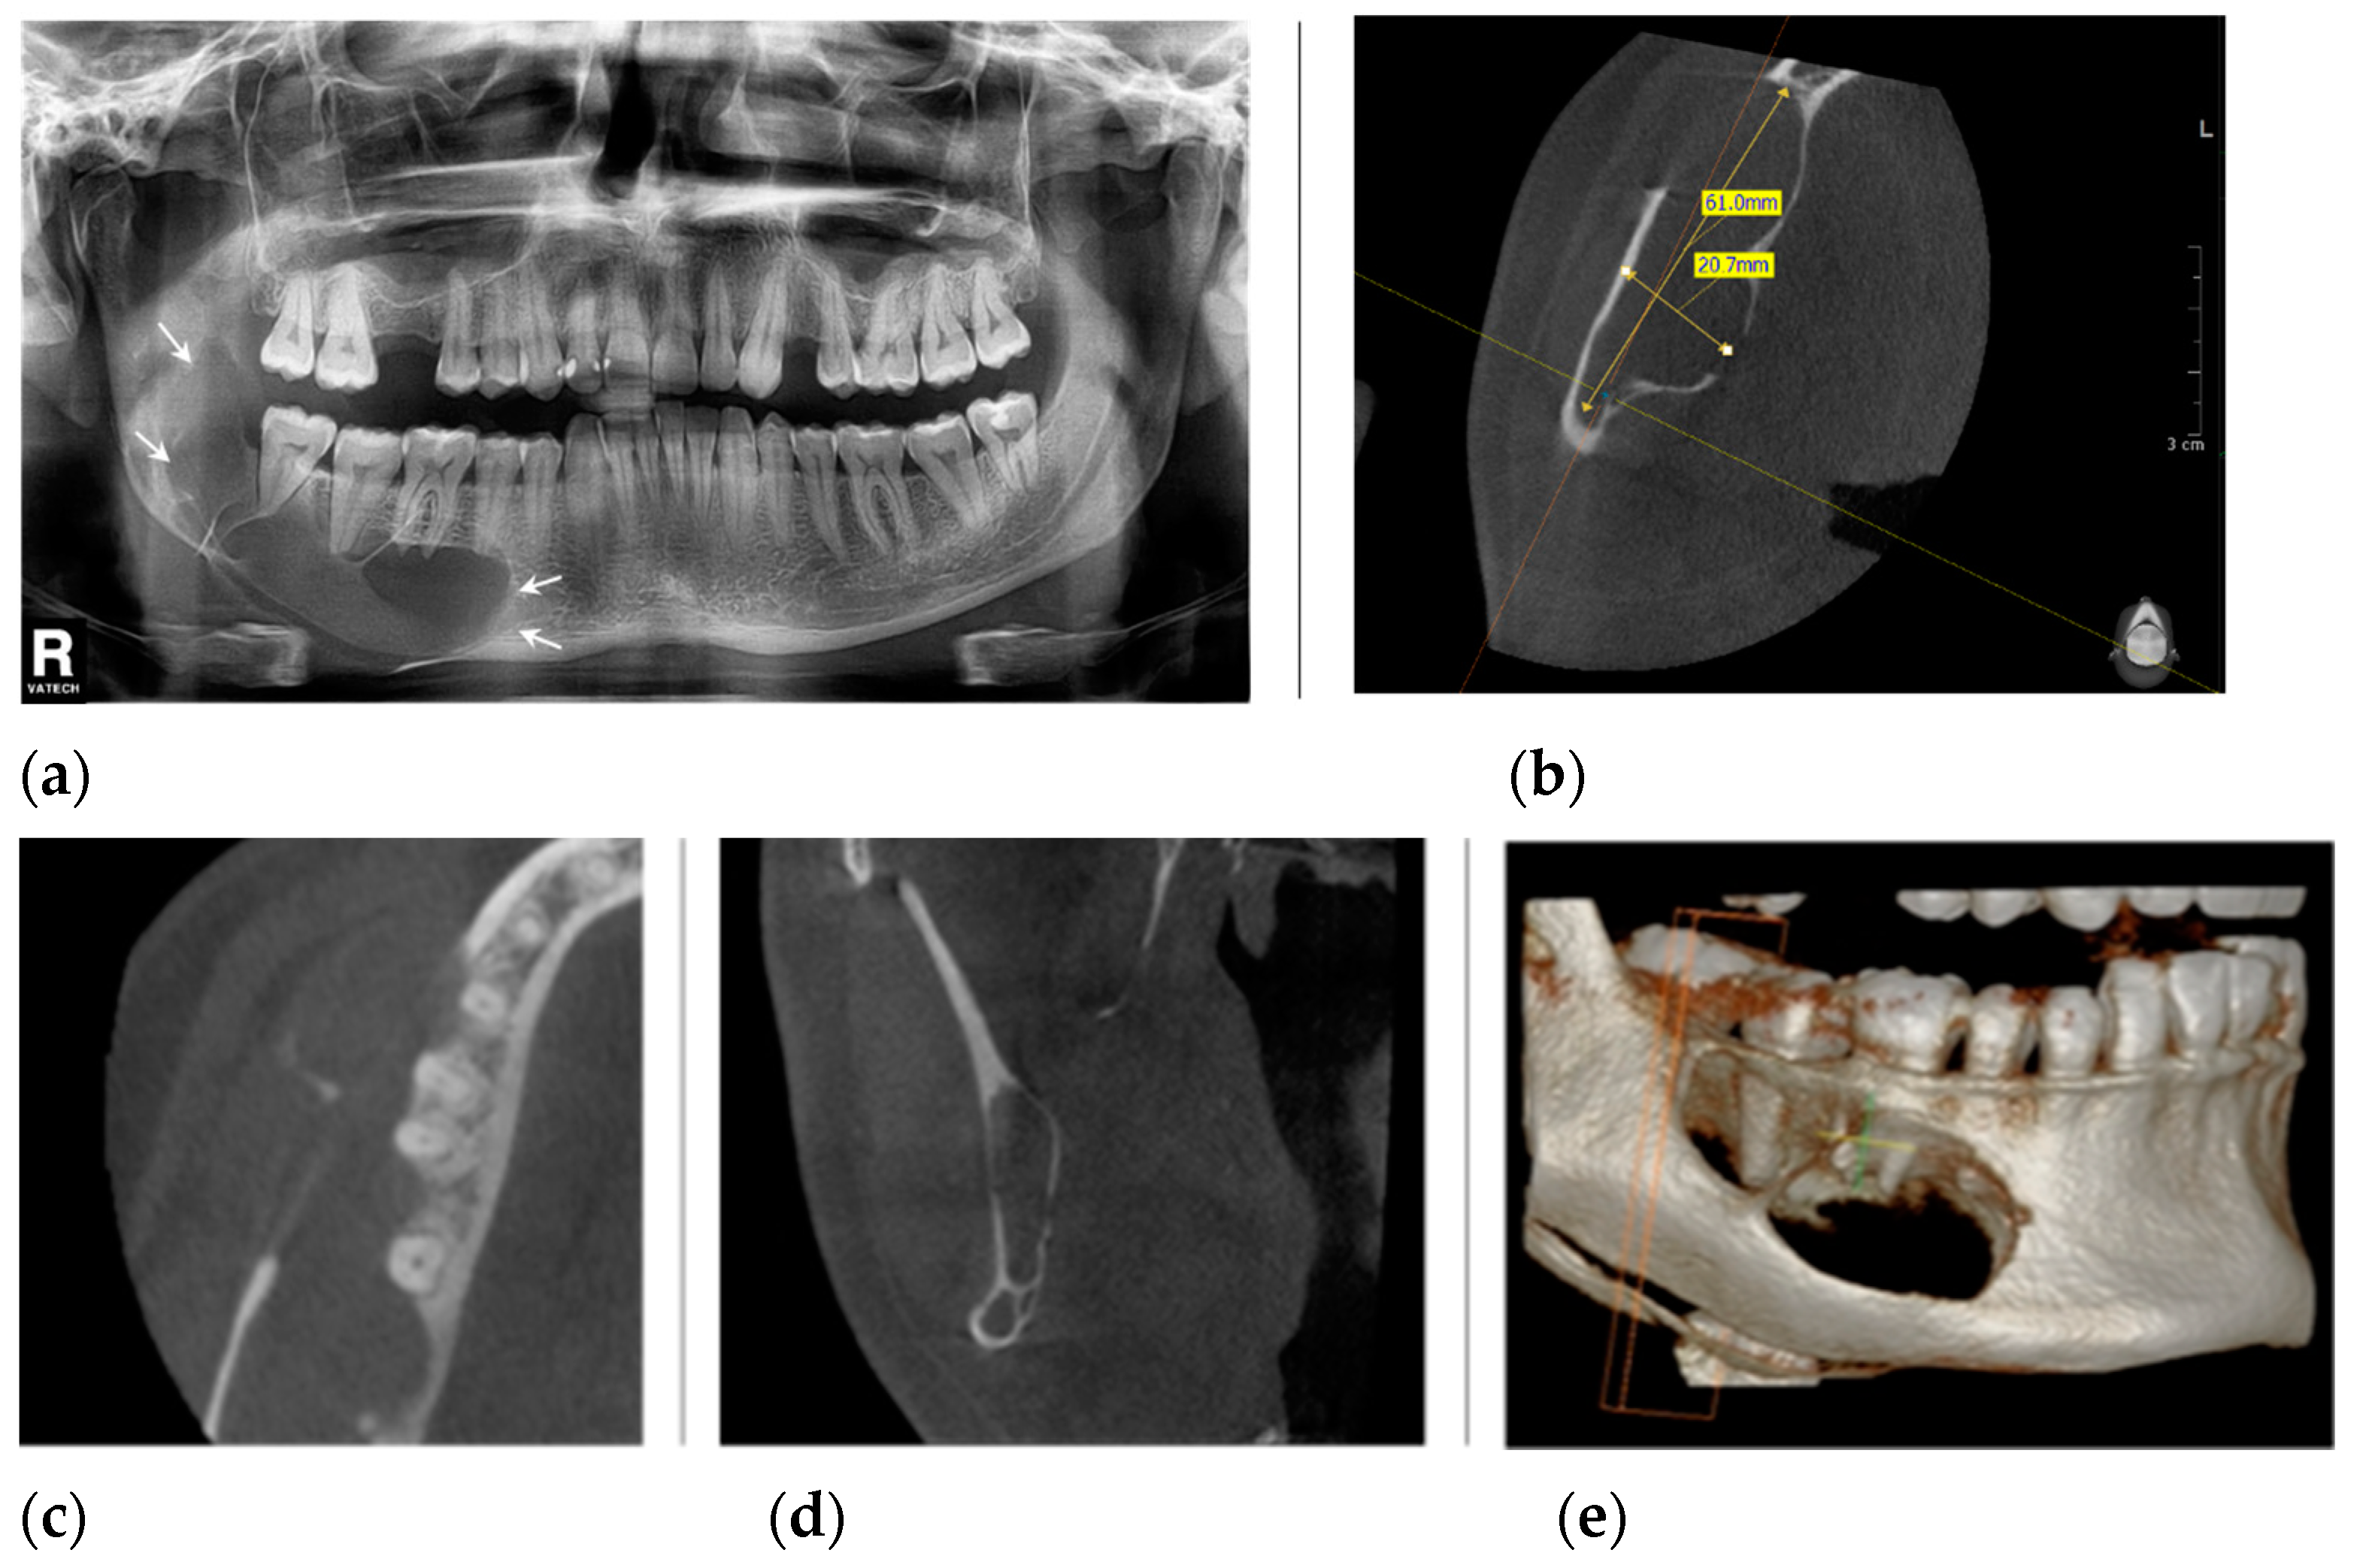

2. Case Presentation